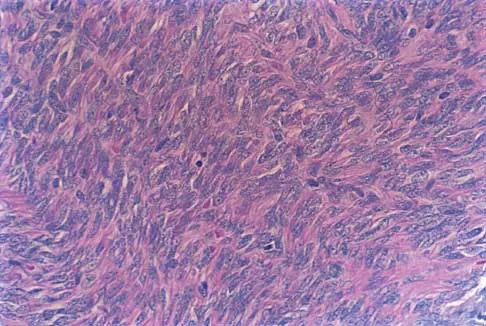

Question 57

A 13-year-old boy has pain and a firm mass in his left knee. A radiograph and MRI scan are shown in Figures 2a and 2b, and a biopsy specimen is shown in Figure 2c. Based on these findings, what is the most likely diagnosis?

Explanation